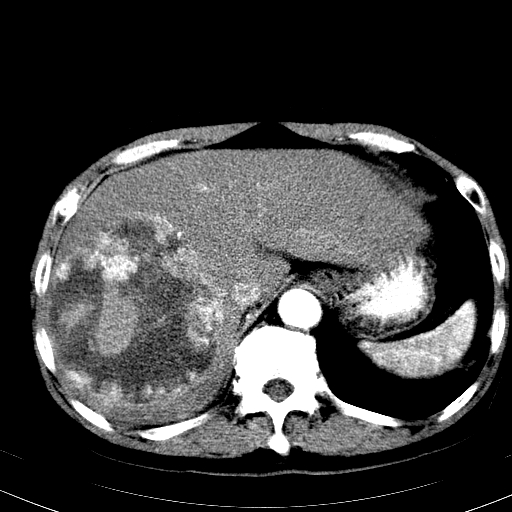

以下是引用卜一在2008-6-23 15:38:00的发言:[br]本例延时期的图象未扫完,单纯平扫 动脉期及门脉期特征分析:平扫低密度较大肿块,内见不规则出血灶,界限清楚。动脉期边缘结节样强化,门脉期病灶边缘进一步强化并范围明显缩小。因此考虑:血管瘤伴出血!

以下是引用hhcckk在2008-6-23 15:10:00的发言:[br]病灶内壁不光滑,中心高密度无强化,考虑肝癌内出血,最后两张横断面是延迟吗?病灶呈低密度。[br][br]鉴别:[br]1、脓肿,内壁光滑,不会发生出血[br]2、血管瘤,早期边缘结节样强化,可合并出血,但延迟后为等密度充填[br]